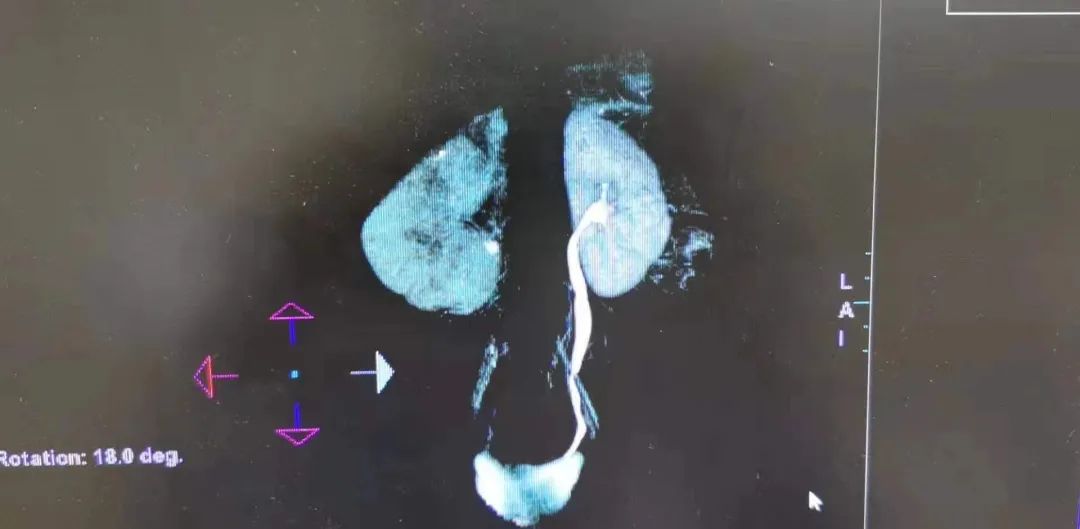

雯雯的影像学资料

1岁的山东女娃雯雯,长相漂亮,懂事腼腆,同病房的病友们称她为 “小可爱”。不久前,雯雯被确诊为输尿管结石,大小为12mm,继发严重的肾积水以及泌尿系感染,积水把小肾脏扩大了,像一个蚕豆样的水球,孩子的父母跑了几家山东著名的三甲医院,都拒绝接受这位可怜的 “结石宝宝” ,医生们认为孩子的病太严重,对于如此小的结石患者该用哪种治疗方案?医生们都无从下手。

11月10日,徐州市中心医院泌尿外科团队在韩从辉副院长与贾建业教授的带领下,赵岩主任、周荣升主任、马伟明博士、蒋博、以及麻醉团队的全力配合下,成功为雯雯行体外冲击波碎石术。术中影像学提示结石粉末化,孩子术后第一次排尿,顺利排出了结石,没有出现血尿,肾积水明显改善!雯雯无任何不适!